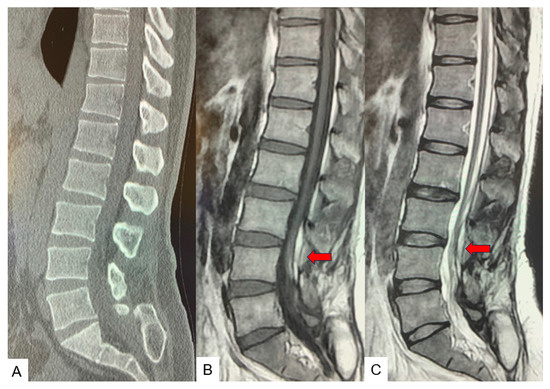

2.3. Preoperative Imaging

2.5. Postoperative Images

3. Case 2: 33-Year-Old Male, Tethered Cord Syndrome, Conventional Technique